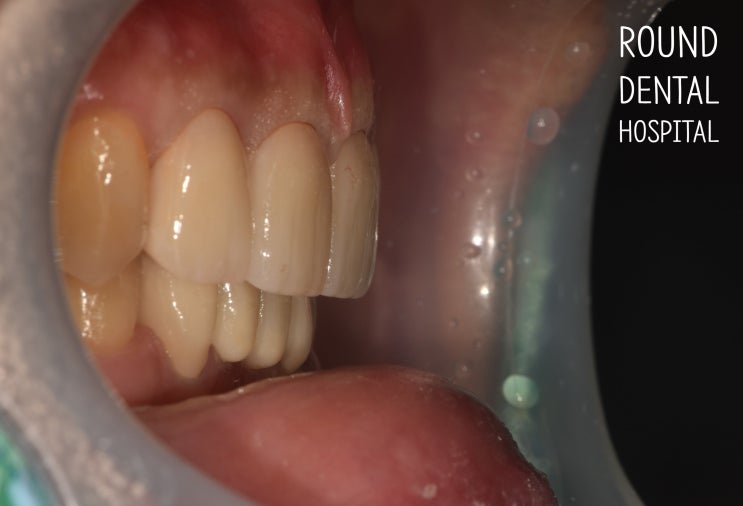

매교동치과 : 깊게 물리는 앞니 보철치료

개원 11주년을 맞이하는 치과병원 라운드치과병원입니다. since 2014 아래 앞니가 깨졌어요. 위아래 앞니를...